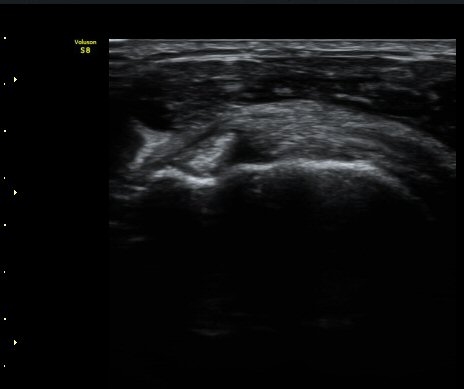

¾î±ú ¾Õ À̵ιڱ٠Ⱦ´Ü¸é°Ë»ç¿¡¼­ ÀÌºÎ¹Ú±Ù°Ç °í¶û ¾Æ·¡ ºÎÀ§¿¡¼­ À̵ιڱ٠ÀåµÎ ÁÖÀ§¿¡

¼ö¾×Àú·ù°¡ °üÂûµÈ´Ù(±×¸² 1, 2). °ß°©ÇÏ±Ù°Ç Á¾´Ü¸é°Ë»ç¿¡¼­ °ß°©ÇϱٰÇÀÇ °üÀý³»ºÎÀ§(±×¸² 3)